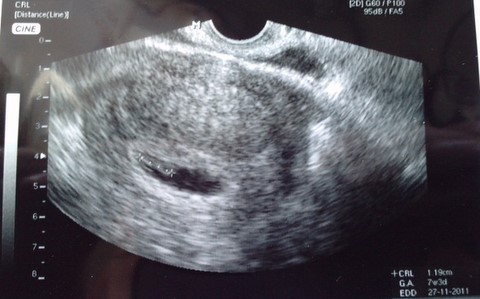

a serduszko bije:-) Czuje sie o niebo lepiej.Moje samopoczucie narazie ok,ale wieczorem mialam takie mdlosci po kawalku ciasta,ze juz stalam nad zlewem,ale nie poszlo.Potem chyba z godzine meczylam sie w lozku zeby zasnac.Ja na slodkie nie bardzo,ale bylismy w gosciach i "no zjedz,musisz troche slodkiego,sama pieklam..." no i zjadlam,a potem zalowalam